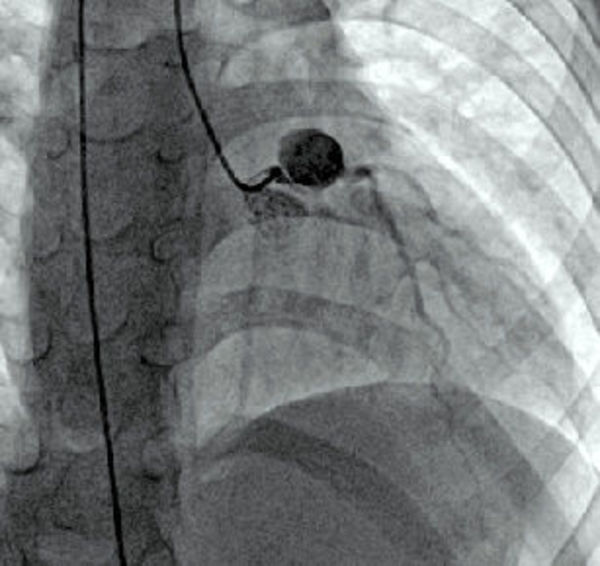

冠状动脉造影显示,左主干巨大冠状动脉瘤形成,位于前降支和左回旋支开口处,瘤体直径约10mm,瘤壁钙化,管腔内有血栓形成,局部狭窄达90%;(见图)。右冠状动脉瘤直径约6mm,局部狭窄约70%;。远端血管管腔均通畅。